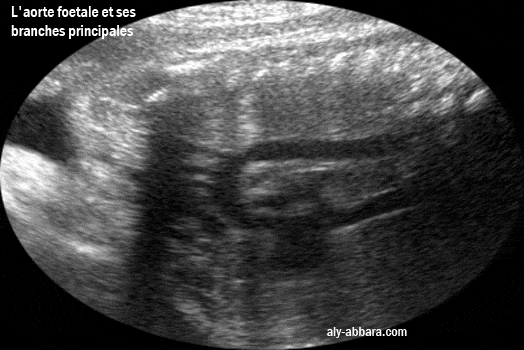

L'aspect échographique de l'aorte ftale avec ses portions et principales branches

Les branches artérielles naissant de la crosse de l'aorte : le tronc artériel brachio-céphalique,

puis l'artère carotide primaire gauche et enfin artère sous-clavière gauche